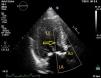

Case reportA 75-year-old woman diagnosed with severe symptomatic aortic stenosis was referred for TAVI. The patient had a history of diabetes, hypertension, coronary artery disease, morbid obesity, and chronic renal failure. Transthoracic echocardiography (TTE) showed sigmoid left ventricular hypertrophy and ejection fraction of 60%, and Doppler echocardiography revealed a mean aortic gradient of 50 mmHg and an aortic valve area of 0.96 cm2 (Figure 1). Transesophageal echocardiography (TEE) carried out for detailed examination revealed sigmoid left ventricular hypertrophy and an aortic annulus diameter of 24 mm. The aortic annulus diameter measured 26 mm×22 mm on multislice computed tomography. The patient was considered to be at too high risk for surgical aortic valve replacement and was referred for TAVI by a transfemoral approach.

The process was performed under deep anesthesia and transthoracic echocardiographic guidance. The TAVI approach was through the right femoral artery using a 26 mm Edwards SAPIEN valve (Edwards Lifesciences, Inc., CA, USA). During balloon inflation under rapid pacing the valve prosthesis immediately embolized into the ascending aorta (Figure 2). Attempts to position the valve in the descending aorta were unsuccessful and the bioprosthesis was re-expanded into the aortic arch between the brachiocephalic trunk and the left common carotid artery. At this stage a second Edwards SAPIEN valve was successfully implanted with gradual balloon inflation (Figure 3). Arch aortography was carried out which showed no aortic regurgitation and no evidence of obstruction of the left common carotid artery or brachiocephalic trunk. The patient was transferred to the intensive care unit in a hemodynamically stable condition and was discharged one week after the procedure.